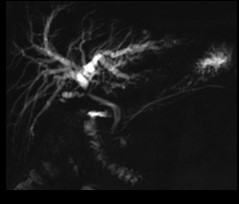

Voie biliaire

Pancreas